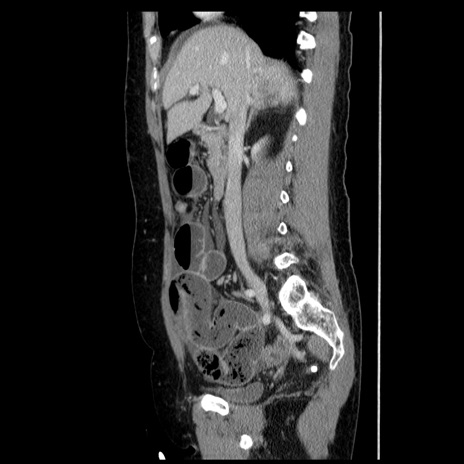

症例6(矢状断像)

【症例】50歳代女性

【主訴】下腹部痛

【現病歴】本日朝より下痢2回あり。 昼食を食べた後、嘔吐3回、下腹部痛認め、症状軽快せず、当院救急搬送。

最終食事:本日昼(生ものなし)。 昨日の夜、刺身を食ぺたとのこと。周囲に同様の症状の者なし。普段、排便は毎日あるとのこと。

【既往歴】卵巣癌術後(8年前に当院で卵巣摘出)

【身体所見】 意識清明、腹部:平坦、腸蠕動音→、やや硬、下腹部自発痛・圧痛あり、反跳痛あり、筋性防御なし。

【データ】WBC 16000、CRP 0.01